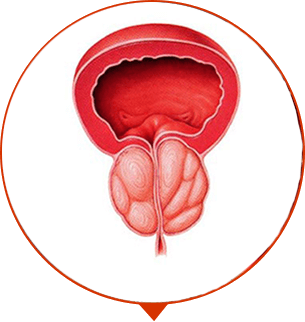

Una revolución en el tratamiento de la prostatitis

PASO1

desparece el dolor, cólico, ardor en la ingle y cintura

PASO 2

la micción se vuelve estable, infrecuente, se elimina la inflamación

PASO 3

se recupera la erección, el organismo se fortaleza, la prostatitis no regresa

ADENOMA DE PRÓSTATA

Crecimiento excesivo del tejido de la próstata, formación del tumor y “nudos”